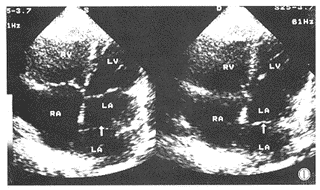

病例例1,男,35岁。2岁发现心脏杂音,运动后心慌、气短30年,加重2年入院检查。查体:体温36.5℃,心律不齐,92次/分,血压14/10kPa。无紫绀及杵状指(趾),双下肢无浮肿,无颈动脉怒张,肝肋下1.0cm,脾未触及,双肺呼吸音清,胸骨左缘3肋间闻及Ⅱ~Ⅲ级收缩期杂音,肺动脉瓣区第二音增强分裂。心电图示心房颤动,右心室肥厚。X线胸片示双肺淤血,心影增大呈二尖瓣型,侧位食道受压,心胸比值0.57。二维超声显示左房、右室内径增大,房、室间隔回声完整,在左房内显示一隔膜状回声将左心房分成二尖瓣侧的主房和肺静脉侧的副房两部分(图1),彩色多普勒血流显像于舒张期显示过左心房内隔膜状中间处五彩镶嵌射流束血流信号,基底部约0.8cm,收缩期显示过二尖瓣少量五彩镶嵌返流束血流信号。诊断房间隔完整的三房心,二尖瓣关闭不全(轻度)。手术所见:心脏中等度增大,以左房、右室增大为主,主肺动脉增粗,在左房内显示一膜状回声将左房分成二尖瓣侧的主房和肺静脉侧的副房两部分,膜状回声中间有一直径约0.5cm孔,房间隔完整。

图1 RA:右心房;RV:右心室;LA:左心房;LV:左心室;S:收缩期;D:舒张期。